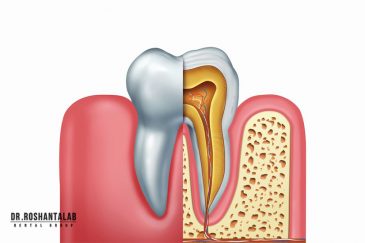

🔸 ایمپلنت دیجیتال و ساخت روکش دیجیتال

طراحی لبخند هالیوودی با متدهای لمینت سرامیکی دندان و کامپوزیت ونیر در کنار اصلاح فرم، خدمات بلیچینگ و روکش دندان، زیبایی چهره شما را تکمیل میکند.ترمیم دندان